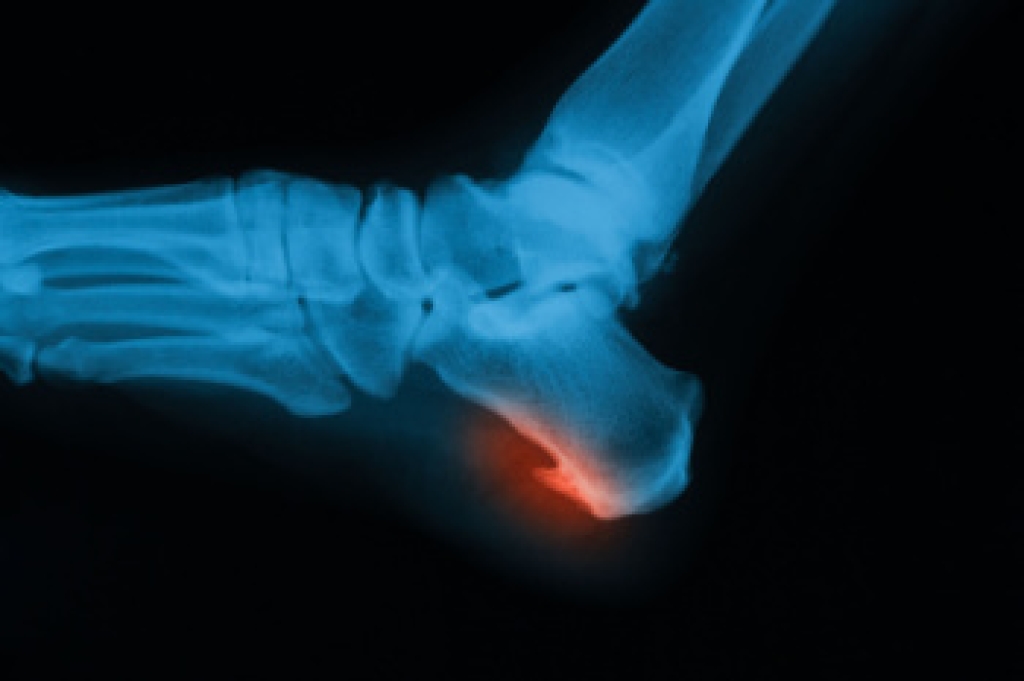

Stretching the muscles in the foot is an important part in any physical activity. Feet that are tight can lead to less flexibility and make you more prone to injury. One of the most common forms of foot pain, plantar fasciitis, can be stretched out to help ease the pain. Stretching can not only ease pain from plantar fasciitis but also prevent it as well. However, it is important to see a podiatrist first to determine if stretching is right for you. Podiatrists can also recommend other ways to stretch your feet. Once you know whether stretching is right for you, here are some excellent stretches you can do.